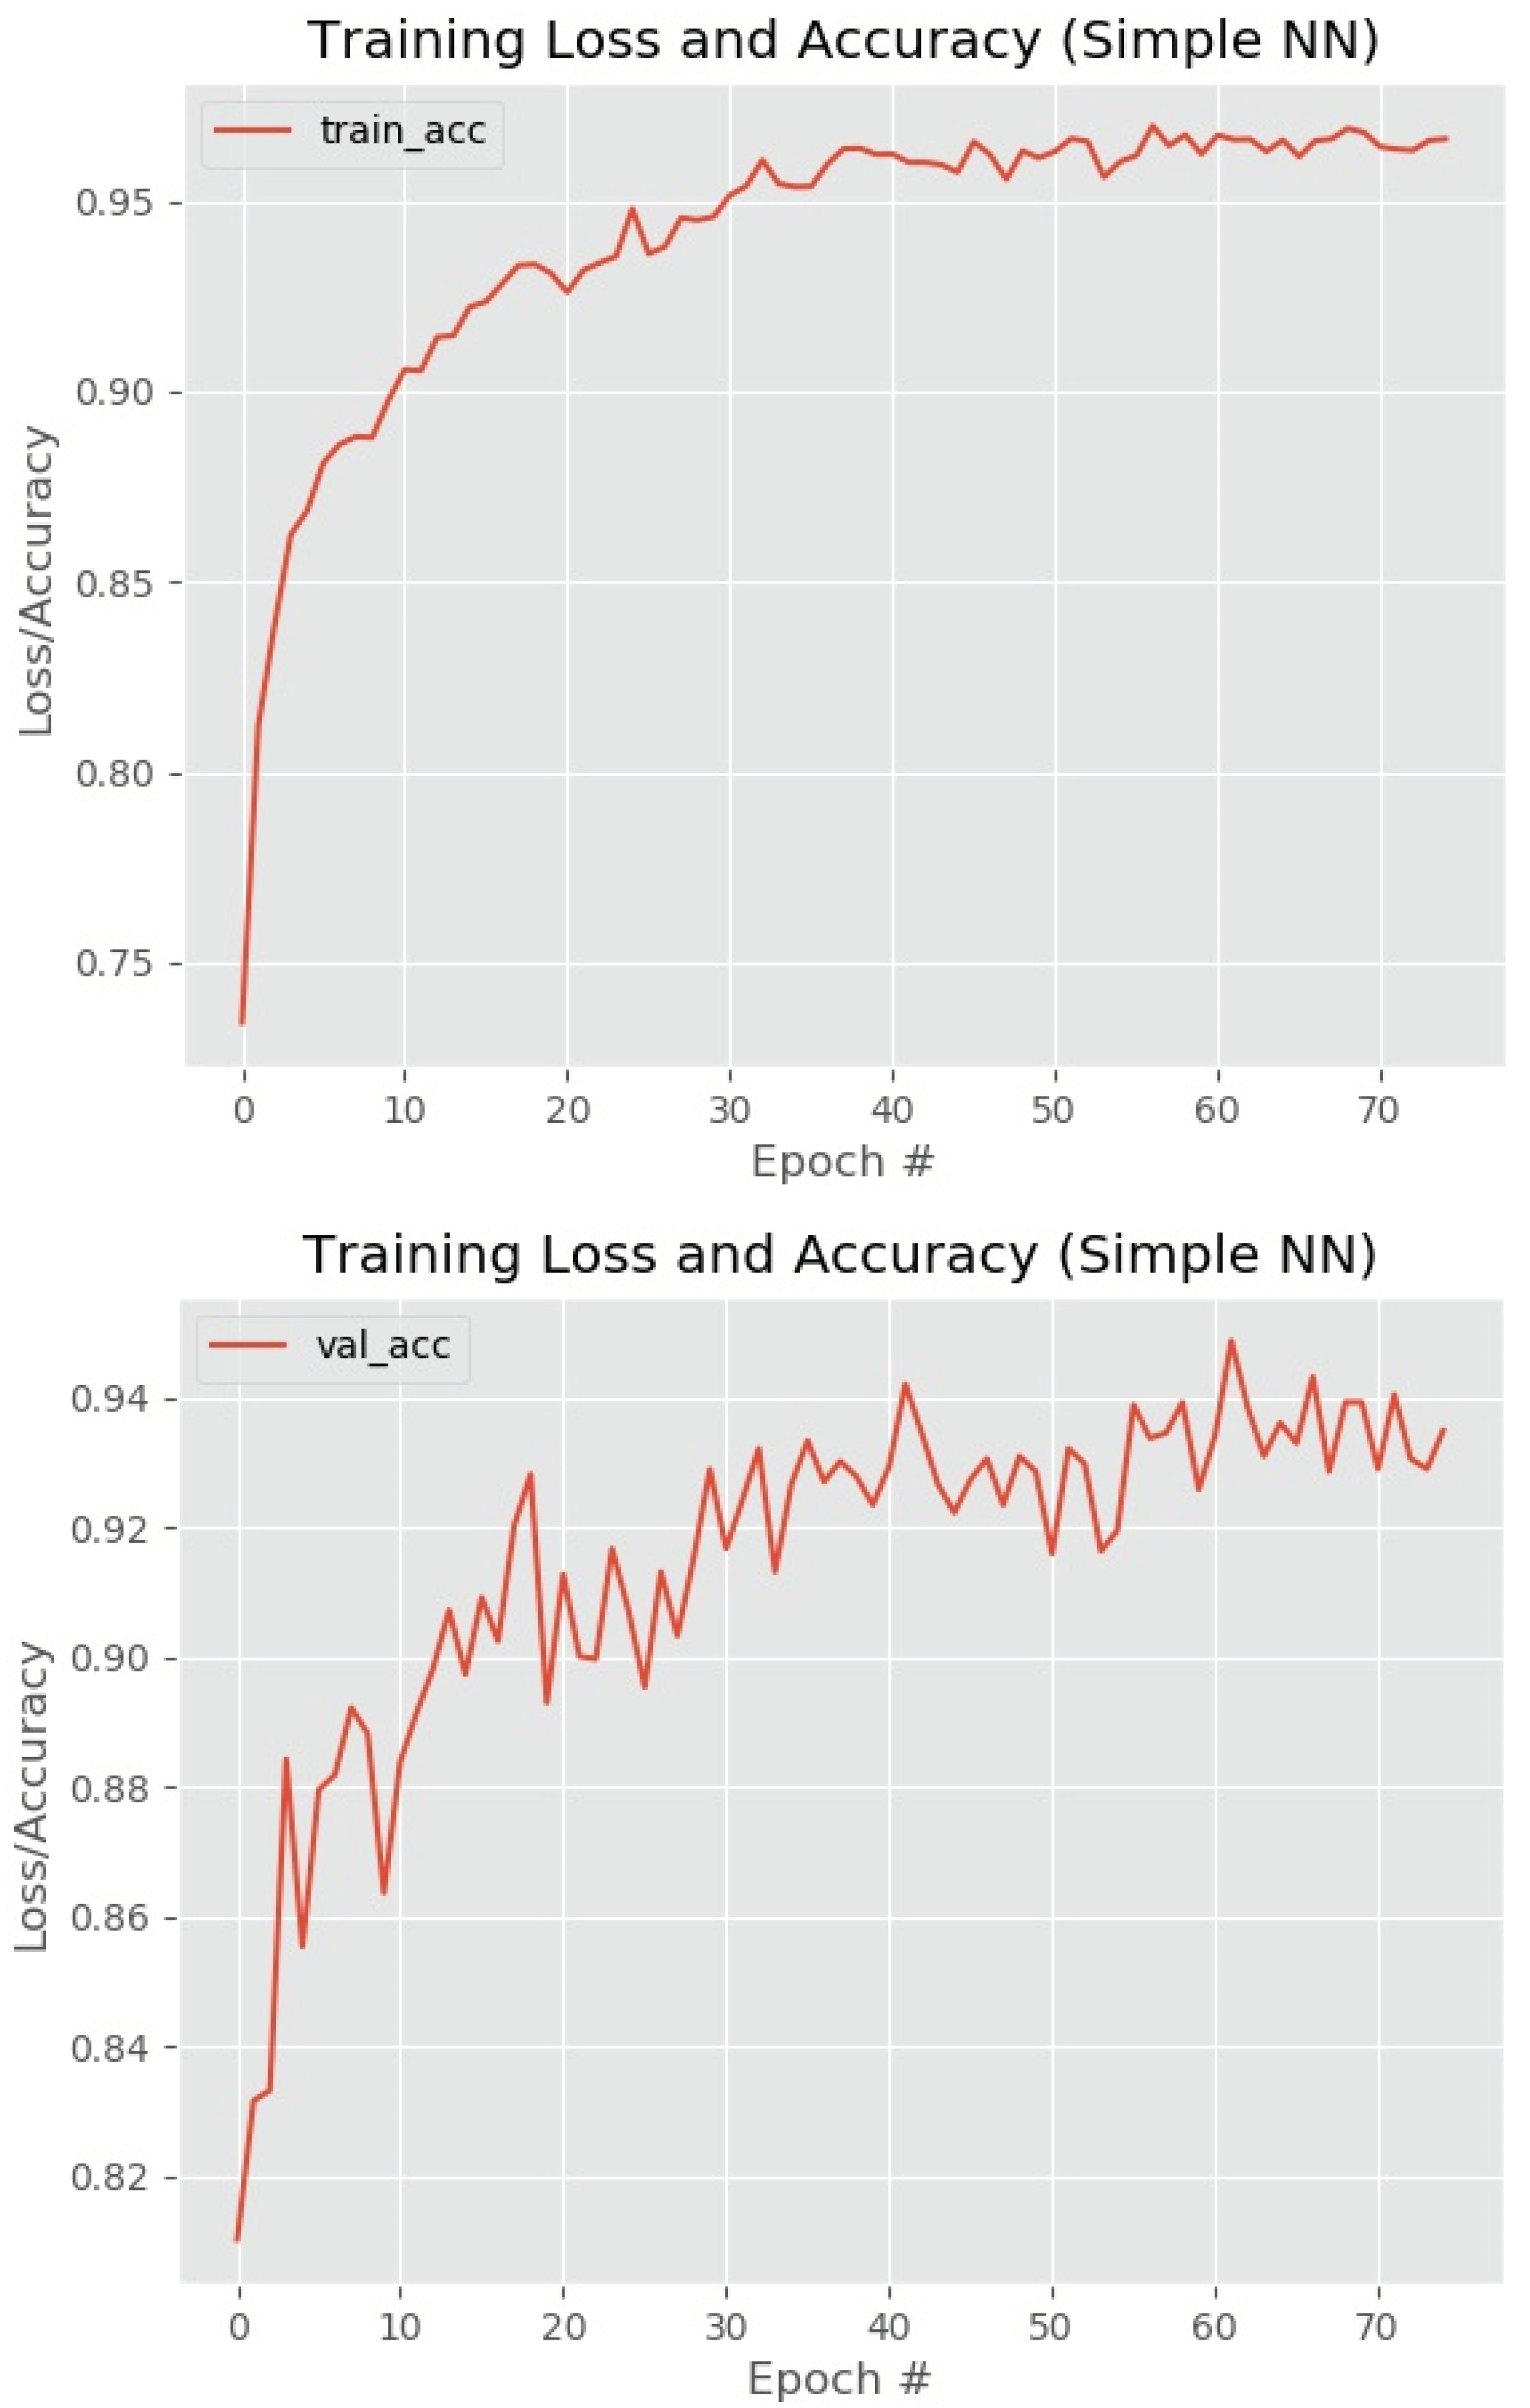

3. Results and Discussion